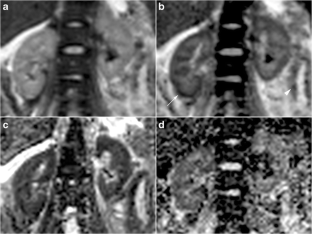

Fig. 1